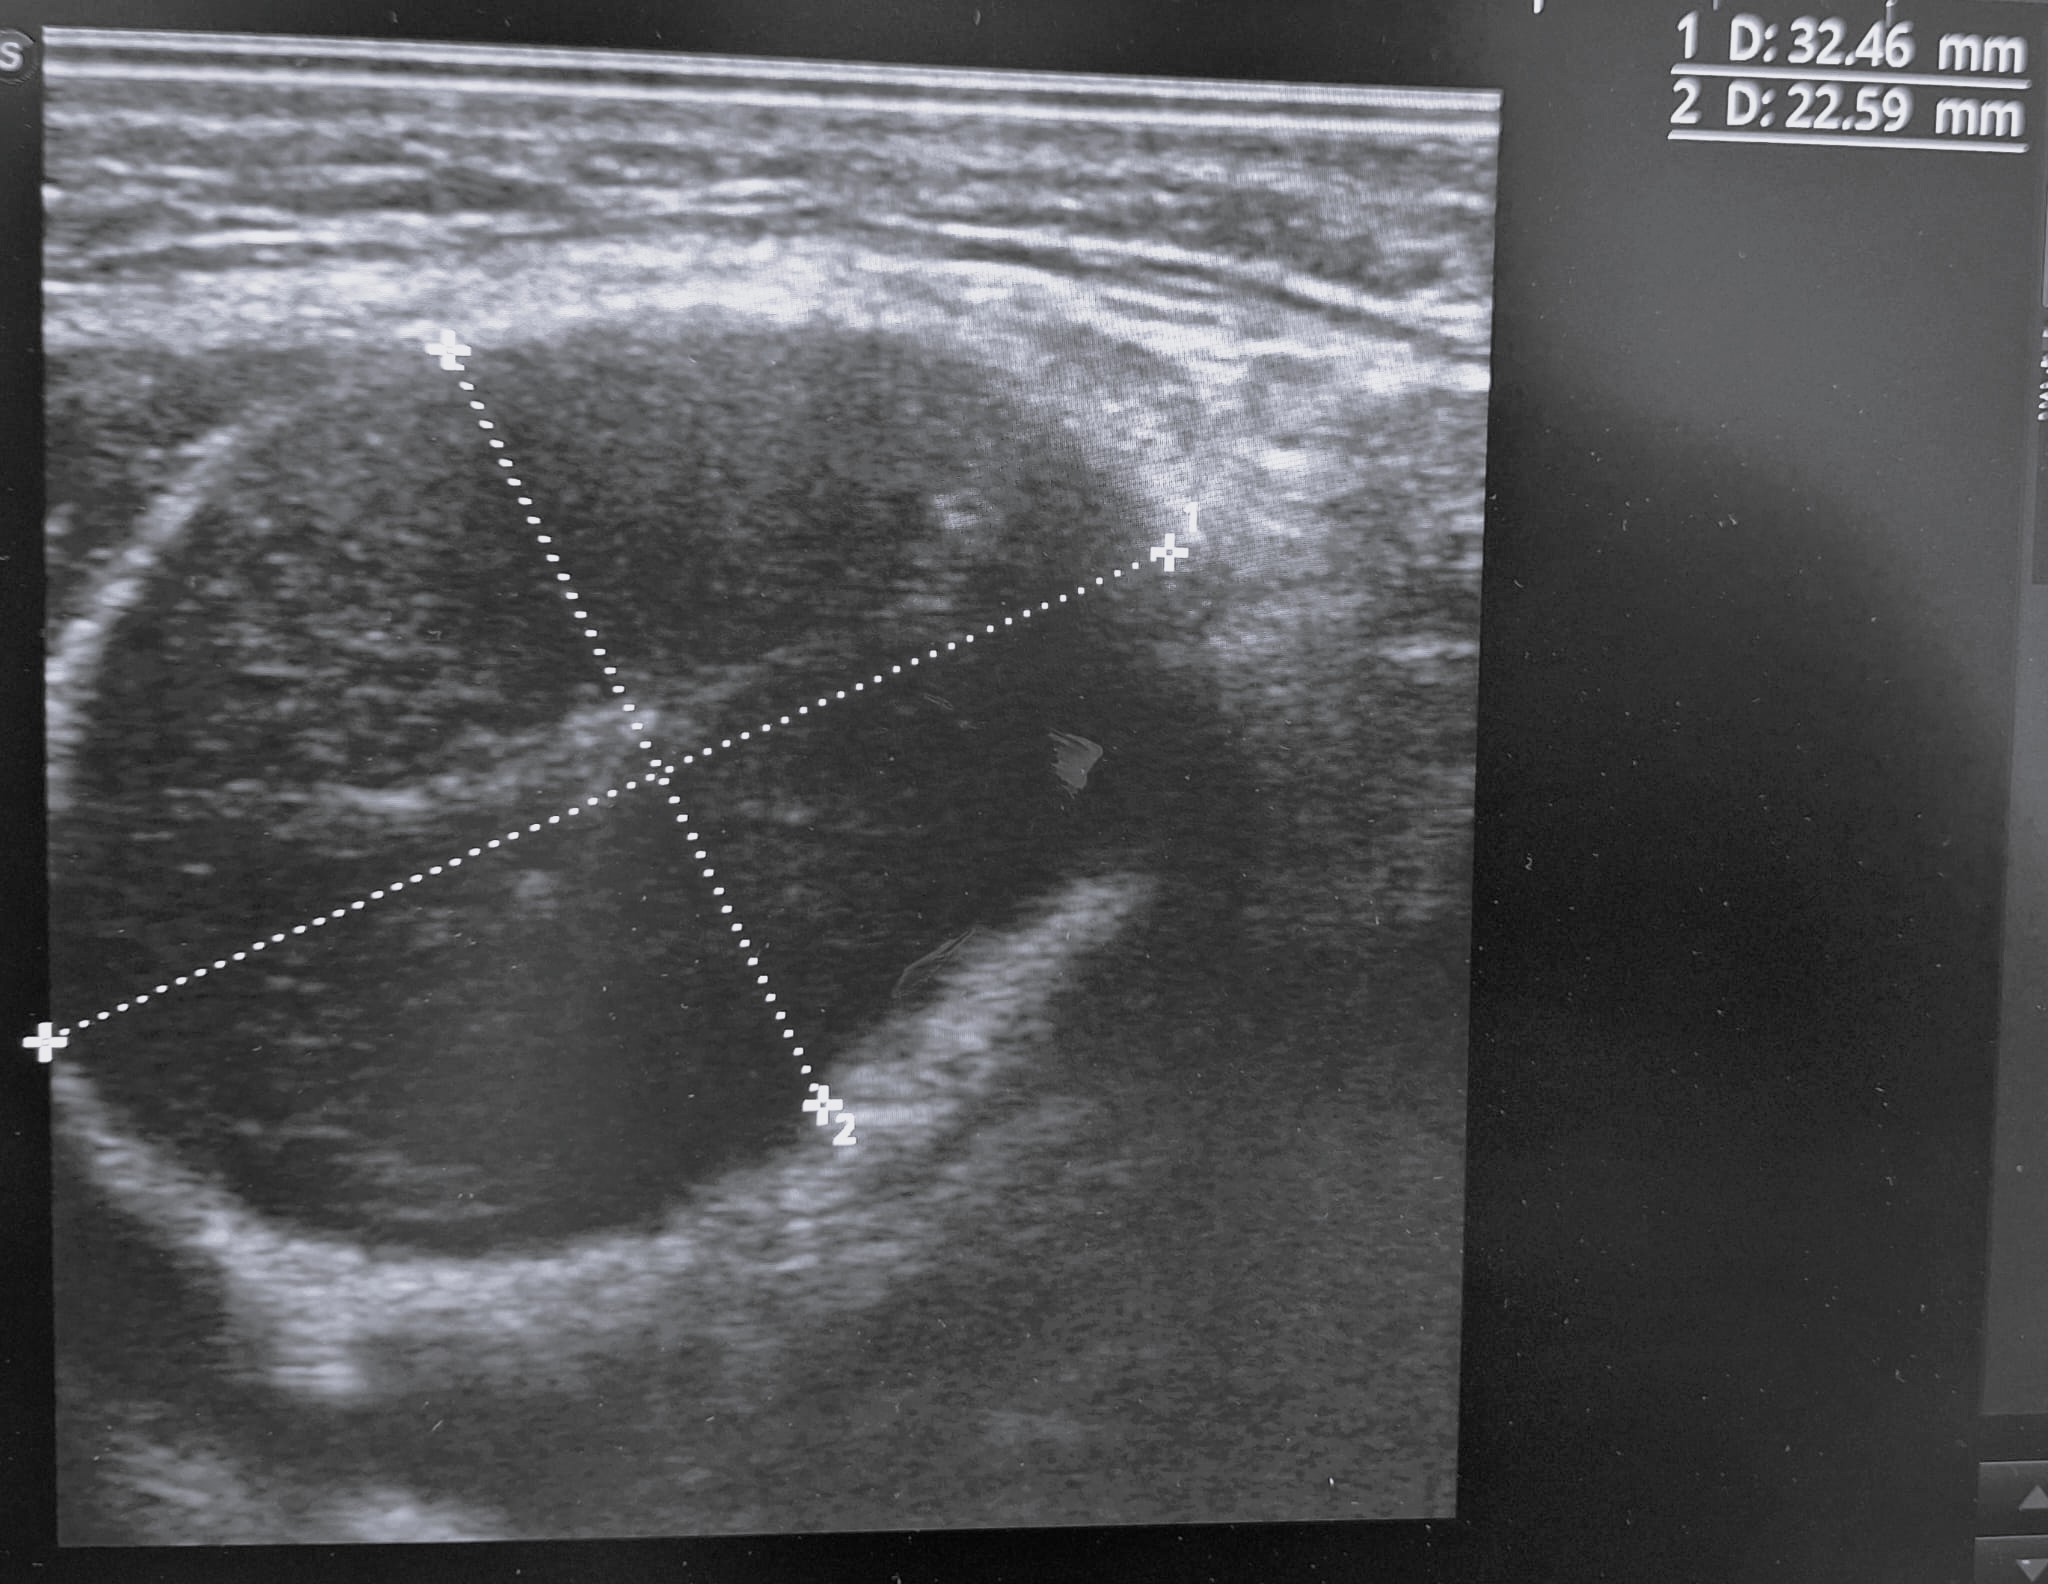

Ecografía de bultoma: se observa masa de 3x2x3 cm en área cervical III derecha, con bordes definidos, discretamente tabicada, con contenido hiperecogénico central, sin captación doppler, compatible con adenopatía patológica versus absceso.